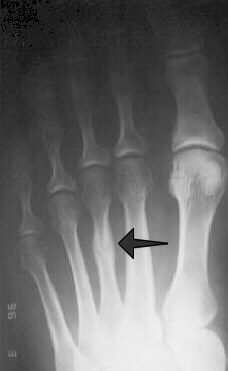

Stress fractures will often present with constant pain that lingers most of the day and doesn’t improve with running or activity. It actually will get worse. Stress fracture pain is also very point tender, meaning the pain is in an isolated area and very sharp when pressing in that area. Stress fractures are most common to the fourth metatarsal in the foot, the tibia of the lower leg, and vary rarely in the heel bone (calcaneal stress fracture). Plantar fasciitis is commonly misdiagnosed as a stress fracture too often after a bone scan is ordered for further examination. MRI is the study of choice to diagnose a stress fracture when it is being considered in any runner. Many times an xray will not show signs of a stress fracture for 2 weeks when and MRI can show immediate changes. This is crucial because altering training patterns for two weeks when waiting for xray changes can be detrimental for any runner.